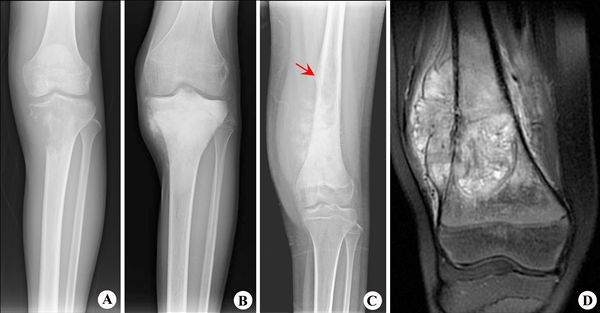

【影像表现】:X线胫骨正位(A)示胫骨上端溶骨性骨肉瘤,呈溶骨性骨质破坏;另一例成骨型骨肉瘤(B),X线平片示胫骨上端磨玻璃状密度增高影;混合型骨肉瘤(C,D),平片(C)示股骨下段骨膜,Cordman三角(↑)和巨大软组织肿块,MRI T2WI脂肪抑制序列(D)示股骨下段骨质破坏,周围伴软组织肿块形成。

【影像诊断】:骨肉瘤。